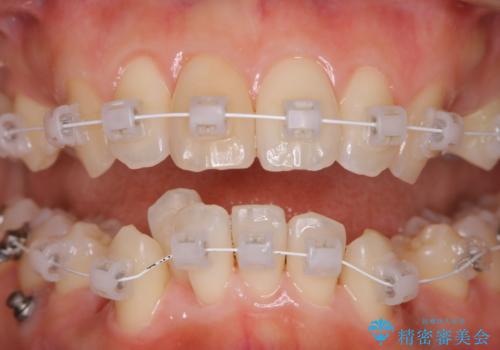

ワイヤー矯正中のクリーニング PMTC

- 審美装置でワイヤー矯正中の患者様です。装置の周りの着色や、抜歯したところのまわりなど全体的な汚れが気になるとのことでPMTC30分コースを行いました。

ワイヤー矯正は歯磨きが難しくなるものです。歯を動かしていることによりできてくるすき間や抜歯矯正の場合は大きなスペースがあります。特にそのような所には汚れがたまりやすくなります。そのため、着色がついたり、虫歯や歯周病、口臭のリスクが高くなります。毎日の歯磨きだけでは100%磨ききることは難しため、ワイヤー調整の診察の際など、定期的にクリーニングすることがおススメです。歯科医院にて、クリーニングを行う場合には、専門的な機械や材料が使用できるため、虫歯・歯周病・口臭などの予防効果も抜群です。